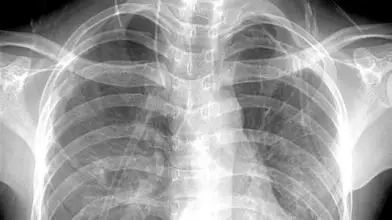

X光:像把面包压扁了看

X光会穿过人体,遇到被遮挡的部位,底片上不会曝光,洗片后这个部位就是白色的。

就像一片面包或一块棉花,看不到里面的纤维纹理,但用手压瘪了会清晰一些。X光最大缺点是受制于深浅组织的影像相互重叠和隐藏,有时需要多次多角度拍摄X光片。